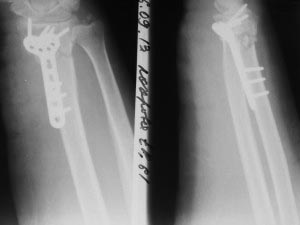

Перелом в "типичном месте" , Вопрос о фиксации шиловидного отростка

локтевой кости...

Оскольчатый перелом дистального метаэпифиза лучевой кости со смещением

отломков. Вопрос по поводу фиксации шиловидного отростка локтевой кости

Хотелось бы узнать мнения и аргументы. Надо ли фиксировать вообще?, если

да, то чем? и почему? Надеюсь на помощь коллег.